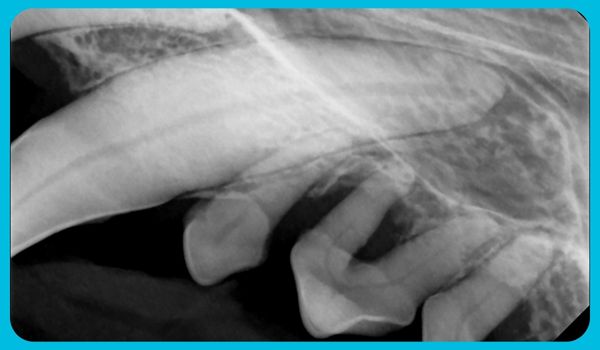

He was placed in foster care while awaiting surgery, where he received patience and comfort as his treatment plan was developed. On November 13, Harley was admitted to our on-site Companion Animal Hospital for his first dental procedure. As part of our advanced protocol, full-mouth dental radiographs were taken—because what lies beneath the gums can’t always be seen. The images revealed extensive disease, requiring a careful, multi-stage approach.

Supported with IV fluids and closely monitored, Harley underwent his first procedure, during which 14 teeth were extracted. He returned to foster care to recover and regain strength before the next stage of surgery.

On December 7, Harley returned for his second procedure. This time, 20 more teeth were carefully removed and sutured, leaving him with just eight remaining teeth. Thanks to the skill and dedication of our veterinary team—including Dr. Dam and our Registered Veterinary Technicians—Harley’s recovery was managed with exceptional expertise and compassion.